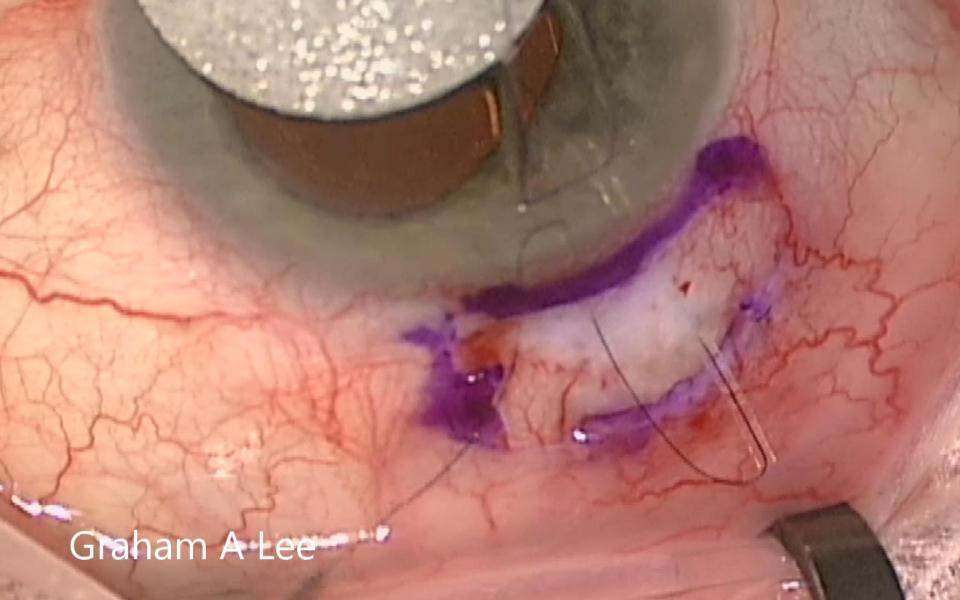

The Trabeculectomy with Preserflo requires revision when the flow is either too low resulting in higher IOP or too high resulting in hypotony. The limbal conjunctival wound must be opened carefully